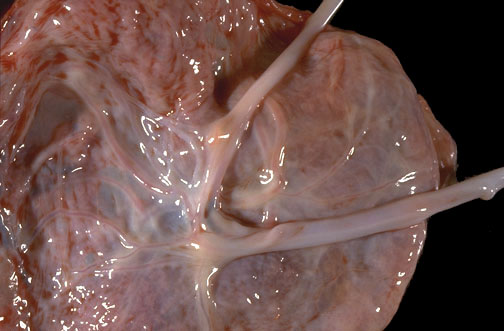

| Only a single amnionic cavity is present in this twin placenta. Note that the two umbilical cords join and share circulation. Monoamnionic twins have more potential problems. In this case, one twin was an "asymmetric" acardiac twin supported by the heart of the remaining complete twin. |